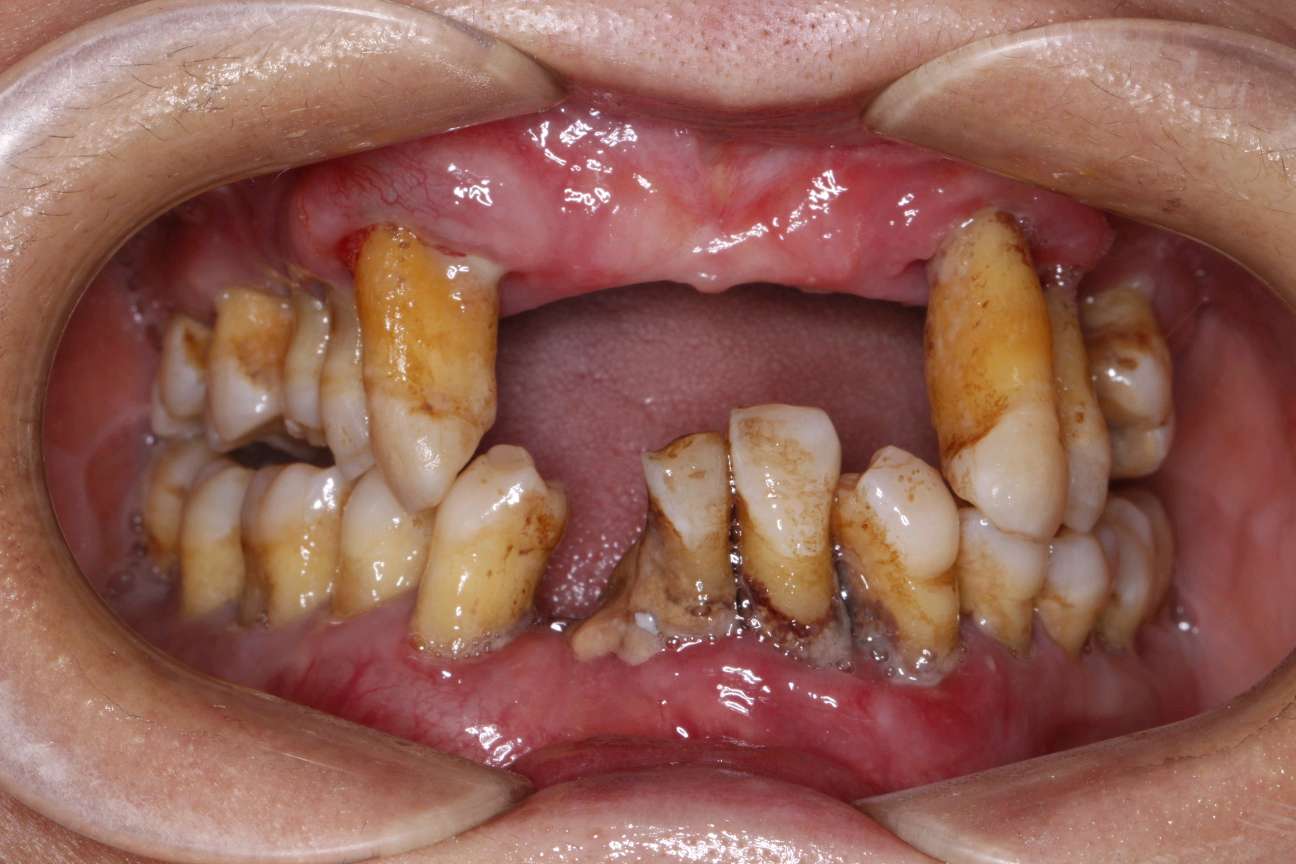

患者女,五十岁,近几年出现刷牙出血和牙齿的松动,甚至部分脱落,近期前来我院就诊。患者全身健康,否认糖尿病,否认家族病史。临床检查:口腔卫生差,可见大量菌斑,软垢。牙石+++,牙龈暗红。根面暴露,前牙部分脱落。X线示牙槽骨吸收至根尖1/3。

看着这摇摆不定的牙齿,让人陷入沉思。很多年轻的牙周炎患者对牙周疾病不重视,可真到了重度牙周炎晚期,牙周组织已经没有支持力,牙齿只会越来越松,甚至脱落。因小失大,得不偿失。所以各位一定要重视口腔卫生,意识到口腔健康的重要性。如果有出现刷牙出血的情况,请及时就医。定期洁牙。